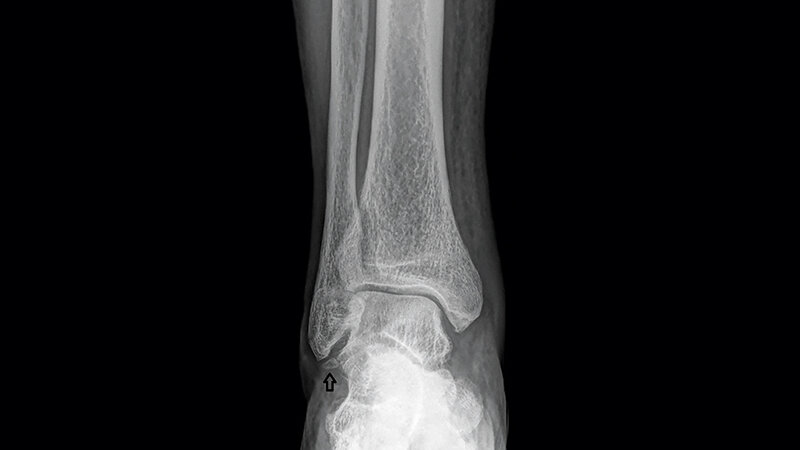

Os subfibulare und subtibiale sind gelegentlich vorkommende akzessorische Knochen des Sprunggelenks. In den meisten Fällen sind sie asymptomatisch. Sie können malleoläre Frakturen vortäuschen. In Fällen von chronischen Schmerzen und Instabilität bei vorliegenden lokalen Akzessoria ist die operative Entfernung die beste Therapie.

Os subfibulare and subtibiale are low prevalence accessory bones of the ankle. In most cases they are not associated with symptoms. They can mimicking malleolar fractures. In cases of chronic pain and instability associated with this accessory bones, surgical ex‧cision is the best therapy.